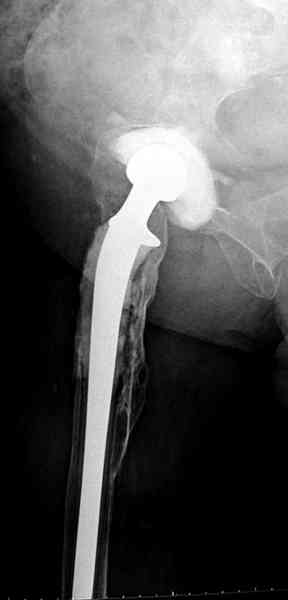

Как-то показывал случай после осложненного тотального эндопротеза,

сперва из-за отсутствия экономических возможности, а затем привыкшая

к своей участи вот уже более 8 лет ходит на временном

"протезе-спейсере".

Полость вертлужной впадины и проксимальное бедро были заполнены

custom made временным протезом из цемента.

Для бедренного компонента можно применить старую длинную ножку

протеза и желательно малого диаметра.